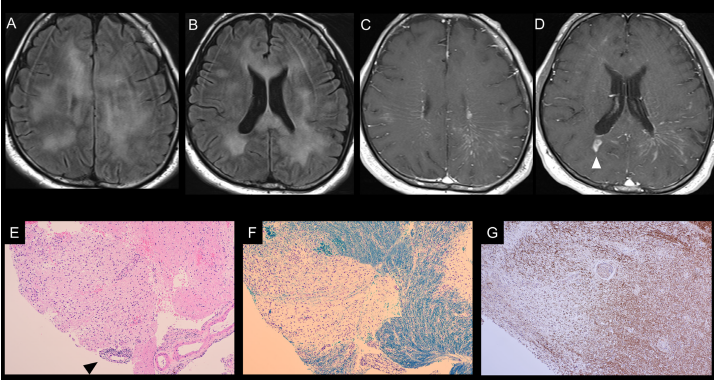

患者出现意识障碍 完全想不到是这种脑病 腾讯新闻

年轻老师患岛叶胶质瘤 德国专家安全全切手术解析 国际神经外科医生集团

硬通道三管齐下治疗丘脑出血并脑室铸型1例